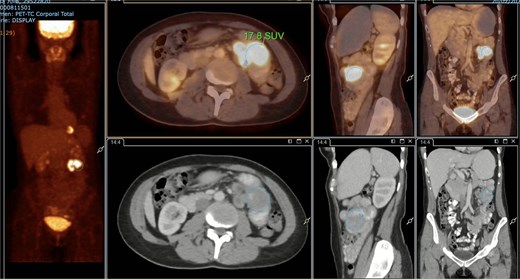

A subsequent PET/CT, performed prior to any surgical intervention, demonstrated intense radiotracer uptake in the thickened jejunal wall (SUV 17.8), in hypermetabolic mesenteric lymph nodes adjacent to the lesion (SUV 15.7), and in a 26.5-mm hypermetabolic nodule in the upper pole of the spleen (SUV 16.4) (Figs 2–4). Given these findings, lymphoma was included in the preoperative differential diagnosis.

PET/CT showing jejunal wall thickening with increased uptake (SUVmax 17.8).